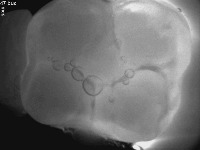

detect caries1 Computer Vision Project

Dental Diagnosis Assistance: This computer vision model can be used by dentists to quickly and accurately identify the presence of caries (decay) in patients' teeth during dental examinations, allowing for more efficient and targeted treatment plans.

Dental Education: The model can be used as a teaching tool for dental students and professionals to learn and differentiate between various decayed and sound dental conditions, improving their diagnostic skills and understanding of dental anatomy.